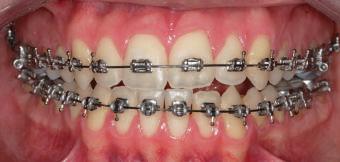

20 Dental Tribune Bulgarian Edition / октомври 2022 г. П ациентите със завършен растеж и скелетни проблеми обикновено представляват предизвикателство за ортодонт ската практика. Необходимостта от изваждане на зъби в комбинация с особеностите на възрастовата ортодонтия изисква особено внима ние. Фокусът върху критично важното значение на позицията на долните резци във връзка с дългосроч ната стабилност и постигането на оптимални оклузални взаимоотношения при затварянето на екстракционните пространства лесно може да излезе извън контрол. Когато към тези чисто кли нични проблеми се добави и стресът от натоваре ната практика, предизвикателството става още по-голямо. Всички тези фактори налагат използ ването на доказан подход с ясни и последовател ни стъпки, в което се разкрива силата на дисциплината „Алекзандър“ – предвидим протокол през целия процес на елиминиране на ротациите, ниве лиране на дъгите, затваряне на екстракционните пространства и финализиране на случая. Именно такъв е и случаят, който презентираме –екстракционен, скелетен клас 3 при възрастен па циент, лекуван по системата „Алекзандър“. ПРЕДВИДИМИ РЕЗУЛТАТИ ПРИ ПАЦИЕНТИ СЪС ЗАВЪРШЕН РАСТЕЖ И СКЕЛЕТЕН КЛАС 3, ИЗПОЛЗВАЙКИ ЕКСТРАКЦИОННО ЛЕЧЕНИЕ ПО ДИСЦИПЛИНАТА „АЛЕКЗАНДЪР“ Д-р Радой Димитров, България Преди започване на лечение клиничен случай | ортодонтия Фиг. 1а–1e Преди започване на лечение. Пациентът пристига в практиката с основното оплакване от невъзмож ност за нормално дъвчене. Снета е цялата необходима диагностична ин формация. Фиг. 1f–1h Снимки в профил и анфас. Фиг. 1i–1k Панорамна снимка, телерентгенография и анализ на телерент генография. Фиг. 1а Фиг. 1d Фиг. 1f Фиг. 1g Фиг. 1h Фиг. 1e Фиг. 1b Фиг. 1c Фиг. 1i Фиг. 1j Фиг. 1k

closed.

21Dental Tribune Bulgarian Edition / октомври 2022 г. ДИАГНОСТИЧНИ РЕЗУЛТАТИ: 1. Възраст на пациента: 21 години 2. Скелетен клас III (ANB 0) 3. Зъбен клас 3 4. Ръбцова захапка във фронта, кръстосана в дисталните участъци 5. Тясна горна челюст 6. Overjet – 0 мм, Overbite – 0 мм 7. Несъответствие на горната с долната средна линия 8. Единични контакти в ЦО 9. Хиподивергентен тип на растеж SN/MP – 33.5 10. Неравен гингивален контур 11. Неравна линия на усмивката 12. Тенденция за рецесии в долен фронт ПРЕПОРЪЧИТЕЛНО ЛЕЧЕНИЕ: Пълно ортодонтско лечение с метални брекети „Алекзандър“ Корекция на клас 3 захапката в областта на кучешките зъби с екстракция на първите пре молари в долна челюст Корекция на кръстосаната захапка в дистални участъци Коригиране на ръбцовата захапка във фронта Подобряване на ОJ и OB на пациента Стрипинг в долен фронт Подреждане на зъбите в горната и долната челюст Професионално хигиенизиране и профилактични дентални прегледи са препоръчителни на всеки 6 месеца. 1-ви месец След 1 месец са залепени брекети в горната челюст – поставена е еластична дъга. 016 NiTi. В долната челюст са елиминирани ротациите, поставена е стоманена дъга. 016SS, закалена с ток, и еластична верижка за затваряне на пространствата. 3-ти месец В долната челюст е поставена трета дъга – 17 x 25 NiTi с къси лигатури и верижка

В горната челюст се затварят пространствата с дъга .016SS и верижка. 5-и месец На 5-ия месец след залепяне на брекетите в долната челюст е поставена стоманена дъга 16 x 22 SS с четвъртито сечение, омега луп и тай бек. В горната челюст е поставена дъга 17 x 25 NiTi. Поради липсата на стабилни оклузални контакти са поставени лингвални верижки в областта на моларите, за да се предотврати нежелана ротация на 7-ите зъби. 6-и месец На 6-ия месец от началото на лечението са екстрахирани долните първи премолари, поставена е дъга 16 x 22 SS със затваряща чупка teardrop. Чупката се активира всеки месец по 1 мм с чинч-бек. клиничен случай | ортодонтия СТЪПКИ НА ЛЕЧЕНИЕТО Начало на лечението Лечението започва с поставяне на апарат за бърза експанзия в горната челюст. През първия месец от лечението са направени 24 оборота на апарата за експанзия. Залепени са брекети в долната челюст, поставена е дъга 17x25 CuNiTi, като са предпи сани клас 3 ластици (1/4”,4 1/2 oz) по време на сън, за да се осигури контрол върху торка на долните резци. Фиг. 2а Фиг. 3a Фиг. 4a Фиг. 3b Фиг. 4b Фиг. 3c Фиг. 4c Фиг. 3d Фиг. 4d Фиг. 3e Фиг. 4e Фиг. 5a Фиг. 5b Фиг. 5c Фиг. 5d Фиг. 5e Фиг. 6a Фиг. 6b Фиг. 6c Фиг. 6d Фиг. 6e Фиг. 7a Фиг. 7b Фиг. 7c Фиг. 7d Фиг. 7e Фиг. 2b Фиг. 2c Фиг. 2d

Dental Tribune Bulgarian Edition / октомври 2022 г.22 клиничен случай | ортодонтия 14-и месец В горната и долната челюст са поставени последни стоманени дъга с омега луп и тай бек – 17 x 25 SS с четвъртито сечение. Назначени е ластик за средната линия в комбинация с клас 3 ластик (1/4”, 6 1/2 oz). Контролни рентгенографии 13-и месец Екстракционните пространства са затворени. Направена е контролна панорамна снимка за оценка позицията на корените. Взето е решение за презалепване на брекетите на 12, 22 и пръстените на 36 и 46. 21-ви месец Средната линия в горната и долната челюст съвпадат. Ластиците са спрени. Свалени са пръстените и брекетите в горната и долната челюст, зигзаг ластици не са използвани поради благоприятните оклузални взаимоотношения. Фиг. 11j Ортопантомография в края на лечението. Фиг. 11k Телерентгенография след края на лечението. Фиг. 11l Анализ на телерентгенографията след лечението. Фиг. 11m Последователност на дъгите в горната и долната челюст Фиг. 11n Суперимпозиция на PreOp и PostOp ортопантомографии. 10-и месец Затварянето на пространствата е предвидимо и контролирано, без да се отварят пространства в зъбната дъга. Фиг. 8a Фиг. 8b Фиг. 8c Фиг. 8d Фиг. 8e Фиг. 10a Фиг. 10b Фиг. 10c Фиг. 10d Фиг. 10e Фиг. 9a Фиг. 9b Фиг. 9c Фиг. 9d Фиг. 9e Фиг. 9f Фиг. 11a Фиг. 11f Фиг. 11j Фиг. 11l Фиг. 11m Фиг. 11n Фиг. 11k Фиг. 11g Фиг. 11h Фиг. 11i Фиг. 11b Фиг. 11c Фиг. 11d Фиг. 11e

Dental Tribune Bulgarian Edition / октомври 2022 г. 23клиничен случай | ортодонтия реклама Лечението е продължило 21 месеца. Проведено е домашно избелване с индивидуални шини. За автора: Д-р Радой Димитров завършва с отличие Факултета по дентална медицина към МУ–София през 2015 г. В продължение на 5 години работи в няколко водещи практики в София, като през 2019 г. заедно със своята съпру га д-р Траяна Димитрова основават собствена практика в гр. Гоце Делчев –Dimitrovi Dental Care. Посещава редица курсове за повишаване на квалификаци ята, но най-сериозен тласък в развитието на ортодонтската си практика получава след завършването на комплексната ортодонтска програма, воде на от д-р Иван Горялов, базирана на дисциплината „Алекзандър“ – система с повече от 50 години опит в целия свят. Д-р Димитров е член на Българския изследователски клуб „Алекзандър“. Взе ма участие като гост-лектор в симпозиума с международно участие The Power of the Alexander Discipline, който се проведе на 14–15.05.2022 г. С д-р Ди митров можете да свържете на тел. +359885 252 025. Заключение Представеният случай е ярък пример за възможностите и красо тата на дисциплината „Алекзандър“ – приложен е утвърден под ход с ясни правила и са постигнати очакваните цели. Резулта тът ще бъде дългосрочно стабилен, тъй като са спазени всички правила, които се отнасят към максимално комфортната пози ция на зъбите в края на лечението. Постигнати са красива усмив ка и стабилна оклузия. ПОСТИГНАТИ РЕЗУЛТАТИ ОТ ЛЕЧЕНИЕТО 1. Коригирана ръбцова захапка 2. Коригирана клас 3 захапка в областта на ку чешките зъби 3. Коригирана кръстосана захапка в дисталните участъци 4. Коригиран овърджет и овърбайт 5. Разширена е горната зъбна дъга 6. Подредени зъби в горната и долната челюст 7. Постигната е стабилна захапка с множество контакти в ЦО 8. Драматично е подобрена дъвкателната функ ция 9. Подобрена е линията на усмивката ДРУГИ ПРОВЕДЕНИ ДЕНТАЛНИ ПРОЦЕДУРИ 1. Домашно избелване на зъбите 2. Екстракция на мъдреците Фиг. 12a Фиг. 12b Фиг. 12c Фиг. 12eФиг. 12d Фиг. 12f Фиг. 12g Информация за дати, цени и отстъпки www.bracescourses.com 0889 22 55 01 Практически курсове лектор д-р Иван Горялов Дисциплината „Алекзандър“ ПЪТЯТ КЪМ СУПЕРУСМИВКИТЕ 100% връщане на цялата сума, ако не сте удовлетворени след преминаване на Ниво 1 Директно и индиректно залепяне на брекети Анализ, диагноза и план на лечение Лечение на клас 2 дълбока захапка Екстракционно лечение Лечение на клас 3 отворена захапка НИВО 5НИВО 1 НИВО 2 НИВО 3 НИВО 4